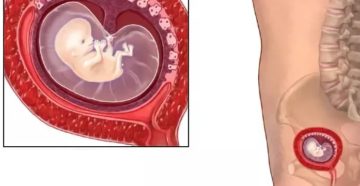

Почему замирает беременность? среда, июля 25, 2012 — 13:13 Невынашивание беременности — патология, при которой…

Причины замершей беременности на 8 неделе ВАЖНО! Для того, что бы сохранить статью в закладки,…